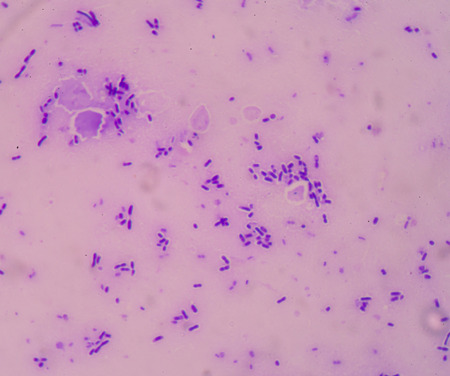

Title: showing title: microscopic view of purple rodshaped bacteria and circular microorganisms in dark background. resolution use.

Dense Clumps of Rod-Shaped Bacteria (Bacilli) Under a Microscope